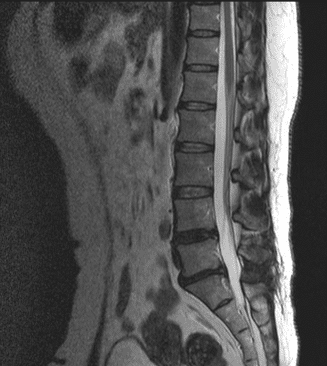

上の写真を見ると神経が圧迫を受けているのがわかります。

正常な腰のMRIで比較すると一目瞭然です。

背骨の後方にある脊髄に圧迫は見られません。